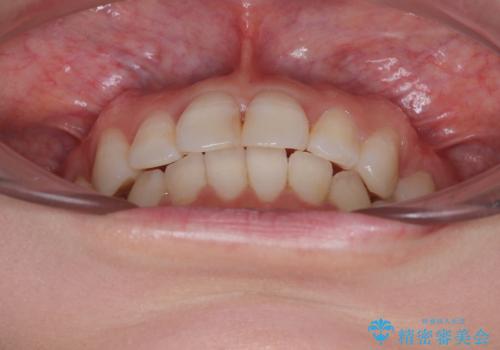

- 上下前歯のデコボコを改善したいとのことで来院された患者様です。

初めの1年くらいは何とか頑張って装着してくださいましたが、途中から変化をあまり感じられなくなり、日々の装着時間は徐々に短くなってしまいました。

前歯のデコボコはもっと改善できましたが、3年半が経過し、初診時と比べたら大幅に良くなったとのことで終了することとなりました。